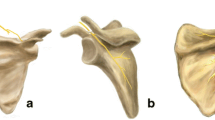

Our data suggest the bony surface of the glenoid is composed of two parts: a circular inferior glenoid and a noncircular cranial extension, of which the supraglenoid tubercle is the most superior and lateral point. This probably can be explained by the development of the bony glenoid where two centers appear during growth. One appears during the 10th year and contributes to the formation of the base of the coracoid and the upper end of the glenoid. It fuses to the scapula during the 15th year. The second one is a horseshoe-shaped ossific center, appearing around puberty, which contributes to the formation of the lower portion of the glenoid [10]. Because the circle always can be defined accurately, the actual circular shape of the prosthetic glenoid base plate can be accepted. However, if the center of this circle is taken as a point of reference for implantation and the base plate is placed onto the glenoid midpoint, 57% will have prosthetic overhang. Therefore, we suggest a smaller base plate. We calculated the mean radius of the glenoid circle to be 14 mm (SD, 1.7 mm). To minimize the loss of bony contact with a smaller base plate we advise using a convex reamer instead of a flat reamer. This would enlarge the contact area of the base plate for the same diameter and would minimize bony resection of the glenoid so the strength of the subchondral plate of the glenoid is minimally weakened. The mean curvature for such a reamer was 34 mm (Fig. 7), which is consistent with reported curvature [25]. Theoretically, a convex base plate improves prosthetic glenoid fixation, as has been documented in anatomic shoulder prostheses [2, 3, 22, 34]. Another implication of this practice is the size of the glenosphere with its center of rotation placed at the glenoid subchondral plate, identical to the original design by Grammont and Baulot, can be smaller than half a sphere without compromising the prosthetic overhang (Fig. 10). This decrease in prosthetic bulkiness eases surgery but lowers the contact area between the prosthetic elements.

In cases where prosthetic overhang cannot be created, we suggest removing part of the infraglenoid tubercle (Fig. 11) on the inferior bony scapular pillar as described below without weakening this pillar since it is the most important supporting structure of the glenoid. The pillars are outlined by three cortices and orientated to the circle formed by the rim of the inferior quadrants of the glenoid. The inferior pillar is directed inferiorly near the lateral border of the scapula [1, 20]. When the proximal portion of the ridge (the most lateral point of the scapular pillar) was imaginarily extended superiorly to the infraglenoid tubercle, our measurements indicated that after flat reaming the glenoid and placing the base plate as distally as possible, 4 mm or 1 mm of the tubercle could be removed just inferior to the glenosphere when using the 36-mm or the 42-mm design, respectively (Table 2) without removing or weakening the scapular pillar. This resection may include the entire infraglenoid tubercle in the glenoid plane of the body. Part of the origin of the triceps brachii muscle will be lost by this resection, but this will not interfere with shoulder stability [13, 17]. We advise preservation of the detached inferior capsule at the tendinous origin of the long head of the triceps tendon to make this resection a safe surgical maneuver; the axillary nerve is protected by doing so.